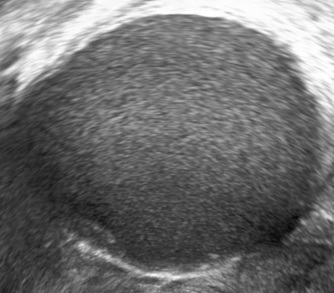

The typical ultrasound features of an endometrioma are:

- ground glass echogenicity (homogeneous low-level echogenicity)

- one to four locules and

- no papillations with detectable blood flow